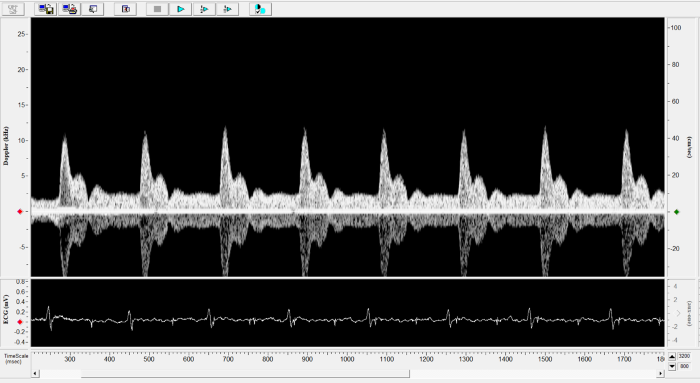

Imaging gallery - Doppler Flow Velocity System

Mouse - Coronary Flow Reserve Imaging. Image Credit: Scintica Instrumentation Inc.